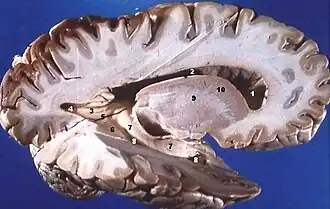

Disección de cerebro humano, vista lateral, mostrando la sustancia gris (zonas más externas y oscuras), y la sustancia blanca (zonas más internas y claramente blancas). | ||

La sustancia blanca (o materia blanca) es una parte del sistema nervioso central compuesta de fibras nerviosas mielinizadas (cubiertas de mielina).[1] Las fibras nerviosas contienen sobre todo muchos axones (un axón es la parte de la neurona encargada de la transmisión de información a otra célula nerviosa). La llamada sustancia gris, en cambio, está compuesta por los somas y cuerpos neuronales, que no poseen mielina, y se la relaciona más con el procesamiento de la información. La materia blanca, que por largo tiempo se pensó que era un tejido pasivo, afecta activamente en cómo aprende y funciona el cerebro. Mientras que la materia gris está asociada principalmente con el procesamiento y el conocimiento, la materia blanca modula la distribución de los potenciales de acción, actuando como un transmisor y coordinando la comunicación entre las diferentes regiones del cerebro.[2]

En el encéfalo la sustancia blanca está distribuida en el interior, mientras que la corteza encefálica y los núcleos de las células del exterior se componen de sustancia gris. Esta distribución cambia en la médula espinal, en donde la sustancia gris se halla en el centro y la blanca en el exterior o periferia.[1][3]